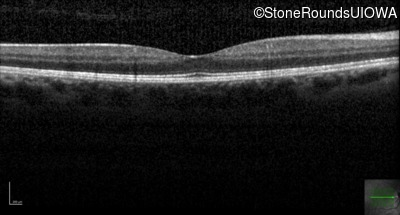

This 44 year old woman has had very poor vision in dim light for her entire life. She vividly remembers running into a picnic table on a bicycle in a campground as a child.